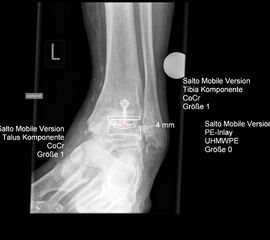

• Prothesenplanung anhand von Röntgenschablonen (Abb. 1 und 2).

• Gewährleistung, daß alle Implantate vorhanden sind.